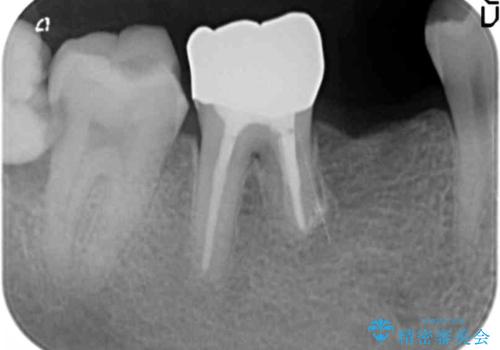

- 右下の奥歯がしみることを主訴に来院された患者様です。

精査したところ、横向きに生えた親知らずのせいで隣の歯(右下7)が虫歯になっていました。

親知らずを抜歯して隣の歯のう蝕を除去し、歯肉の治癒をしっかり待ったのち、患者様のご希望によりゴールド(PGA)クラウンによる補綴を行いました。

右下7:ゴールド(PGA)クラウン